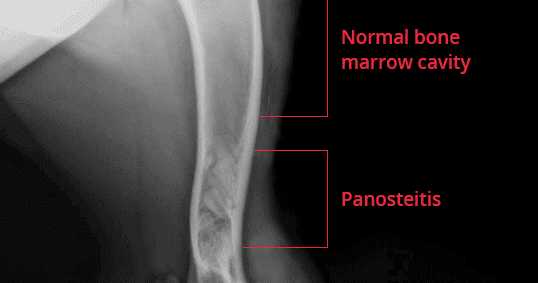

Panosteitis (Pano) or Long Bone Disease in German Shepherd Dog